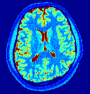

VI-E In-vivo experiments

Two sets of experiments were conducted here: first, we used the 2D and 3D acquisition sequences for scanning a healthy volunteer’s brain (real-world acquisitions). Figures 6 and 7 display the parametric maps reconstructed from 2D spiral and radial readouts. We computed the T1, T2 and proton density (PD) maps using baseline reconstruction algorithms ZF, VS, LR, FLOR, AIR-MRF and our proposed LRTV. While baselines use DM either for quantitative inference or also during reconstruction (i.e. AIR-MRF), we further compare the DM-free LRTV’s performance when cascaded to DM, KM and MRFResnet for quantitative inference. For the 3D spiral acquisitions we compared LRTV and its closest competitor VS in Figure 8. Outcomes from other tested algorithm are displayed in the supplementary materials (Figure S5). Since FLOR does not use dimensionality-reduction, our system ran out of memory during 3D reconstruction; hence results are not reported in this case.